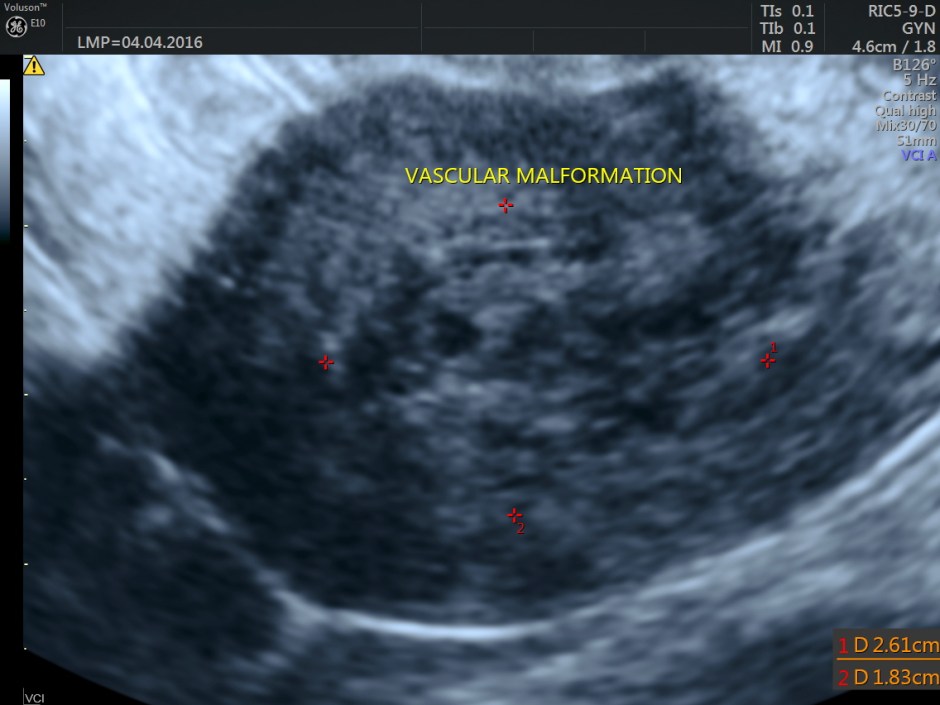

Transvaginal view

Endometrium shows ? polypoid appearance; Irregular hypoechoic myometrial texture with some serpiginous appearance is seen.

The ultrasound diagnosis was a vascular malformation in the uterus .She was referred to an interventional radiologist,who did a CECT the next day.